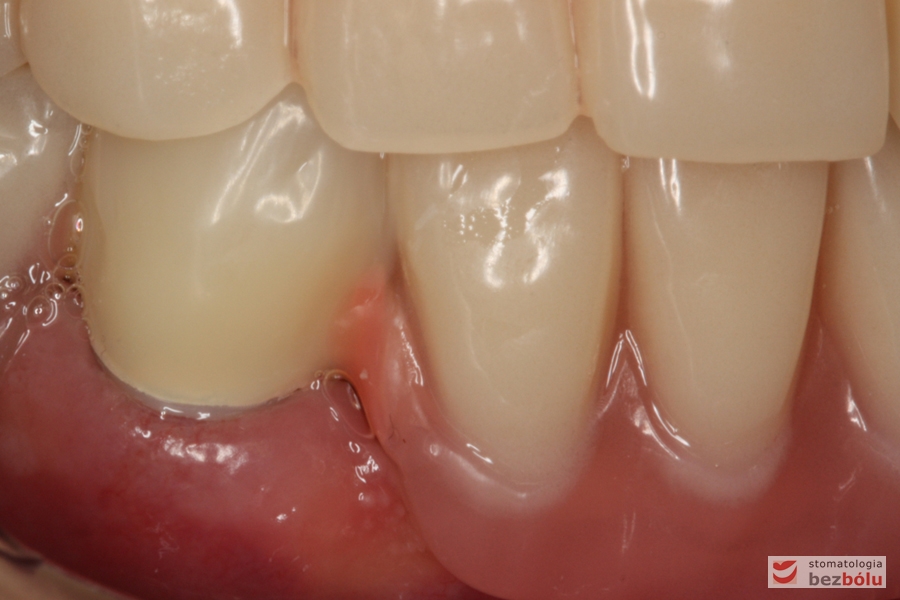

Gotowe patryce koron teleskopowych umieszczone w jamie ustnej na filarach zębów własnych